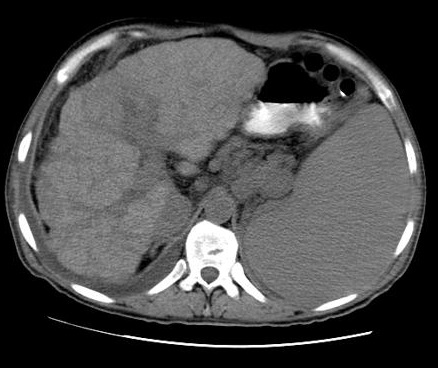

Aspect radiologique TDM de la

cirrhose du foie phase veineuse : Le bord du foie

est irregulier , atrophique , veine porte est dilate

et splenomegalie |

Même cas en coupe a

inferieure de la bifurcation portale : Dilatation de

la veine porte et veine splenique . |

Cirrhose du foie : Aspect de

la surface et parenchyme heterogene nodulaire

, splenomegalie et dilatation de veine splenique

|

Même cas en difference coupe

a travers le tronc portale |